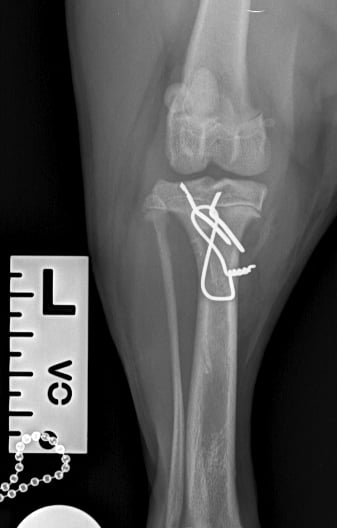

Lateral radiographs revealed a complete avulsion of the left tibial crest (Fig. 1), along with a mild lesion at the distal pole of the patella. For comparison, a lateral view of the right limb is included, demonstrating a normal appearance of the tibial crest growth plate (Fig. 2).

Surgical repair was performed using a medial approach to the proximal tibia. The avulsed tibial tuberosity fragment was identified, anatomically repositioned, and stabilized with two 1.2 mm Kirschner pins and a 1 mm tension band wire (Figs. 3 and 4).

Fig. 1

Fig. 3